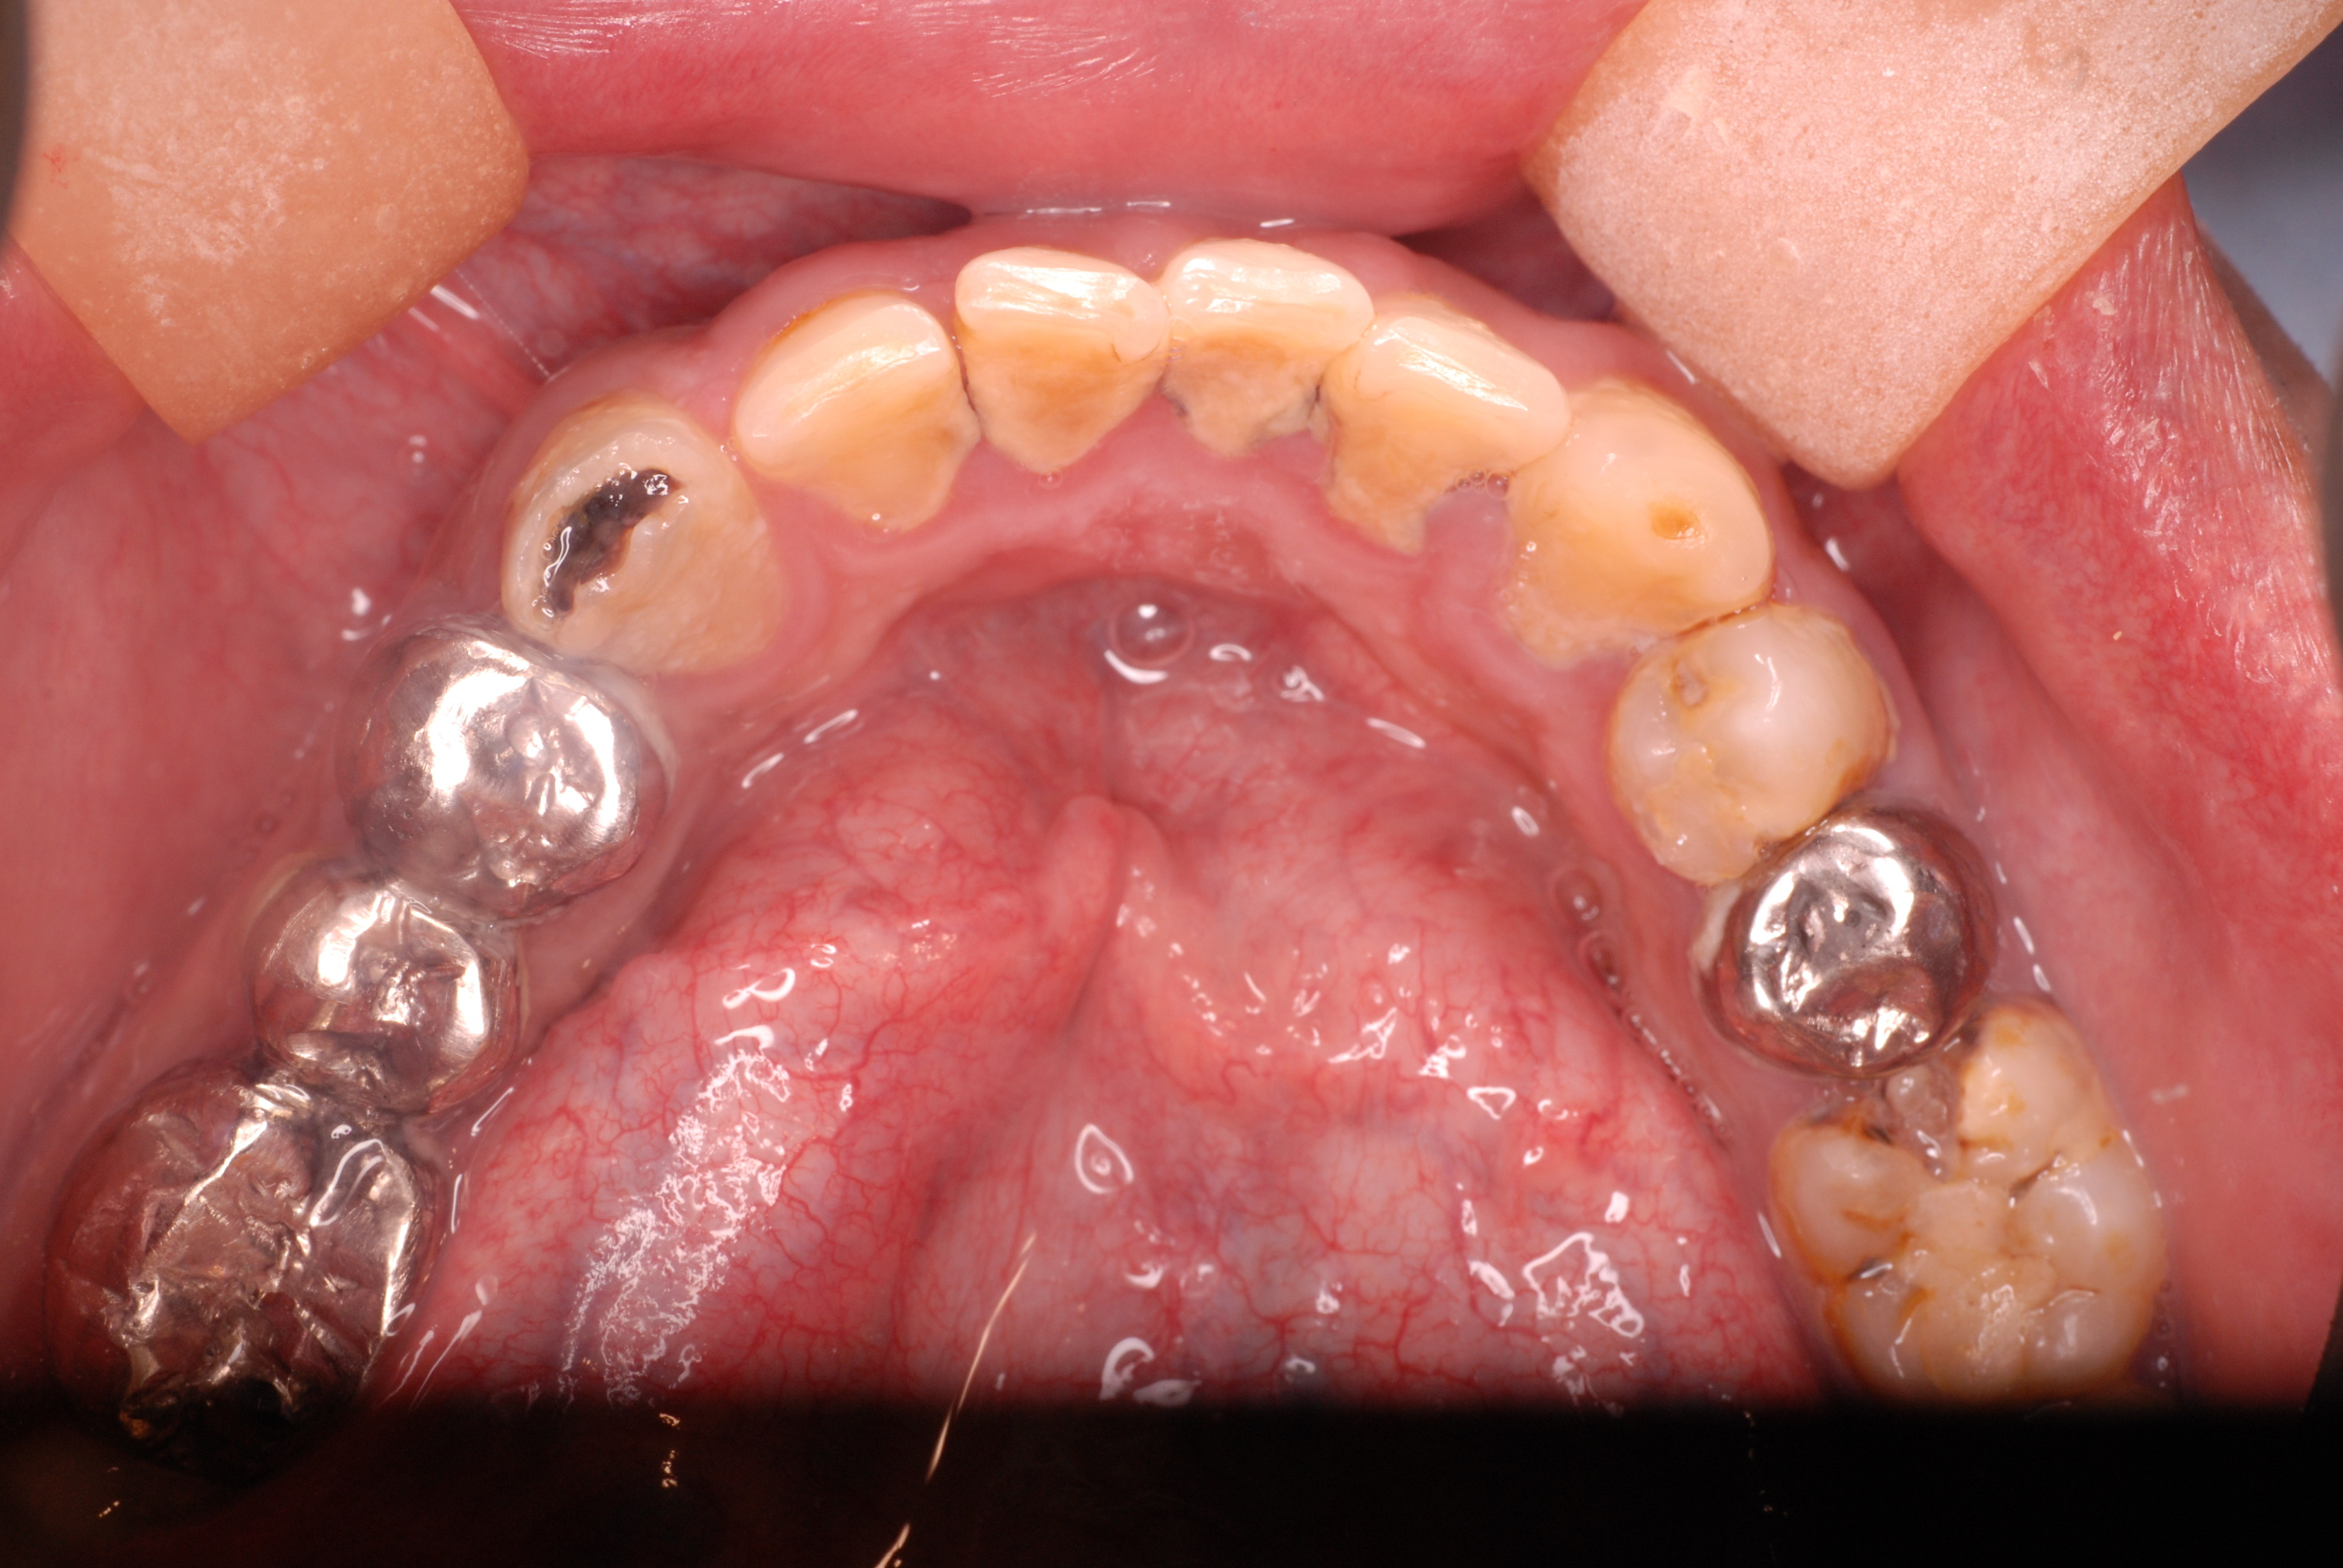

歯無しにならない長い話し

今回約1年近くかかった方のとりあえずの治療が終了しました。

最初の状態です。若いのにすぐ外れる入れ歯をいれていらっしゃいました。

DSC_0167DSC_0162

DSC_0166DSC_0165

DSC_0164

そしてひとまず終了した状態です。

DSC_0018DSC_0023

DSC_0027

このように綺麗になりましたが元の健康な状態になったのではないのです。ばい菌が歯の周りから採れていなければ元の木阿弥。

おそらく差し歯にもできず入れ歯かインプラントという人工歯根になる事でしょう。いやはやいくら費用がかかるのやら患者さんのことながらため息が出ます。

歯医者では病気を治していないことが多いのです。ただ詰めたり被せたりしているのに過ぎません。注意しないともっとひどいことになります。

そして、虫歯や歯周病、そして神経の処置は医療行為ですから誰でも100%うまくいくかというと、うまくいっていないことが多いのです。医療行為は難しいのです。良い歯の医者に当たる事を祈ります。

歯に何かを被せることは医者のやることではなくお口の大工さんがやることなのです。ですから歯医者は、大工と医者を同時にやっていることになりますね。

歯医者から口腔科の医師へ脱皮しなければなりません。日々精進あるのみ!